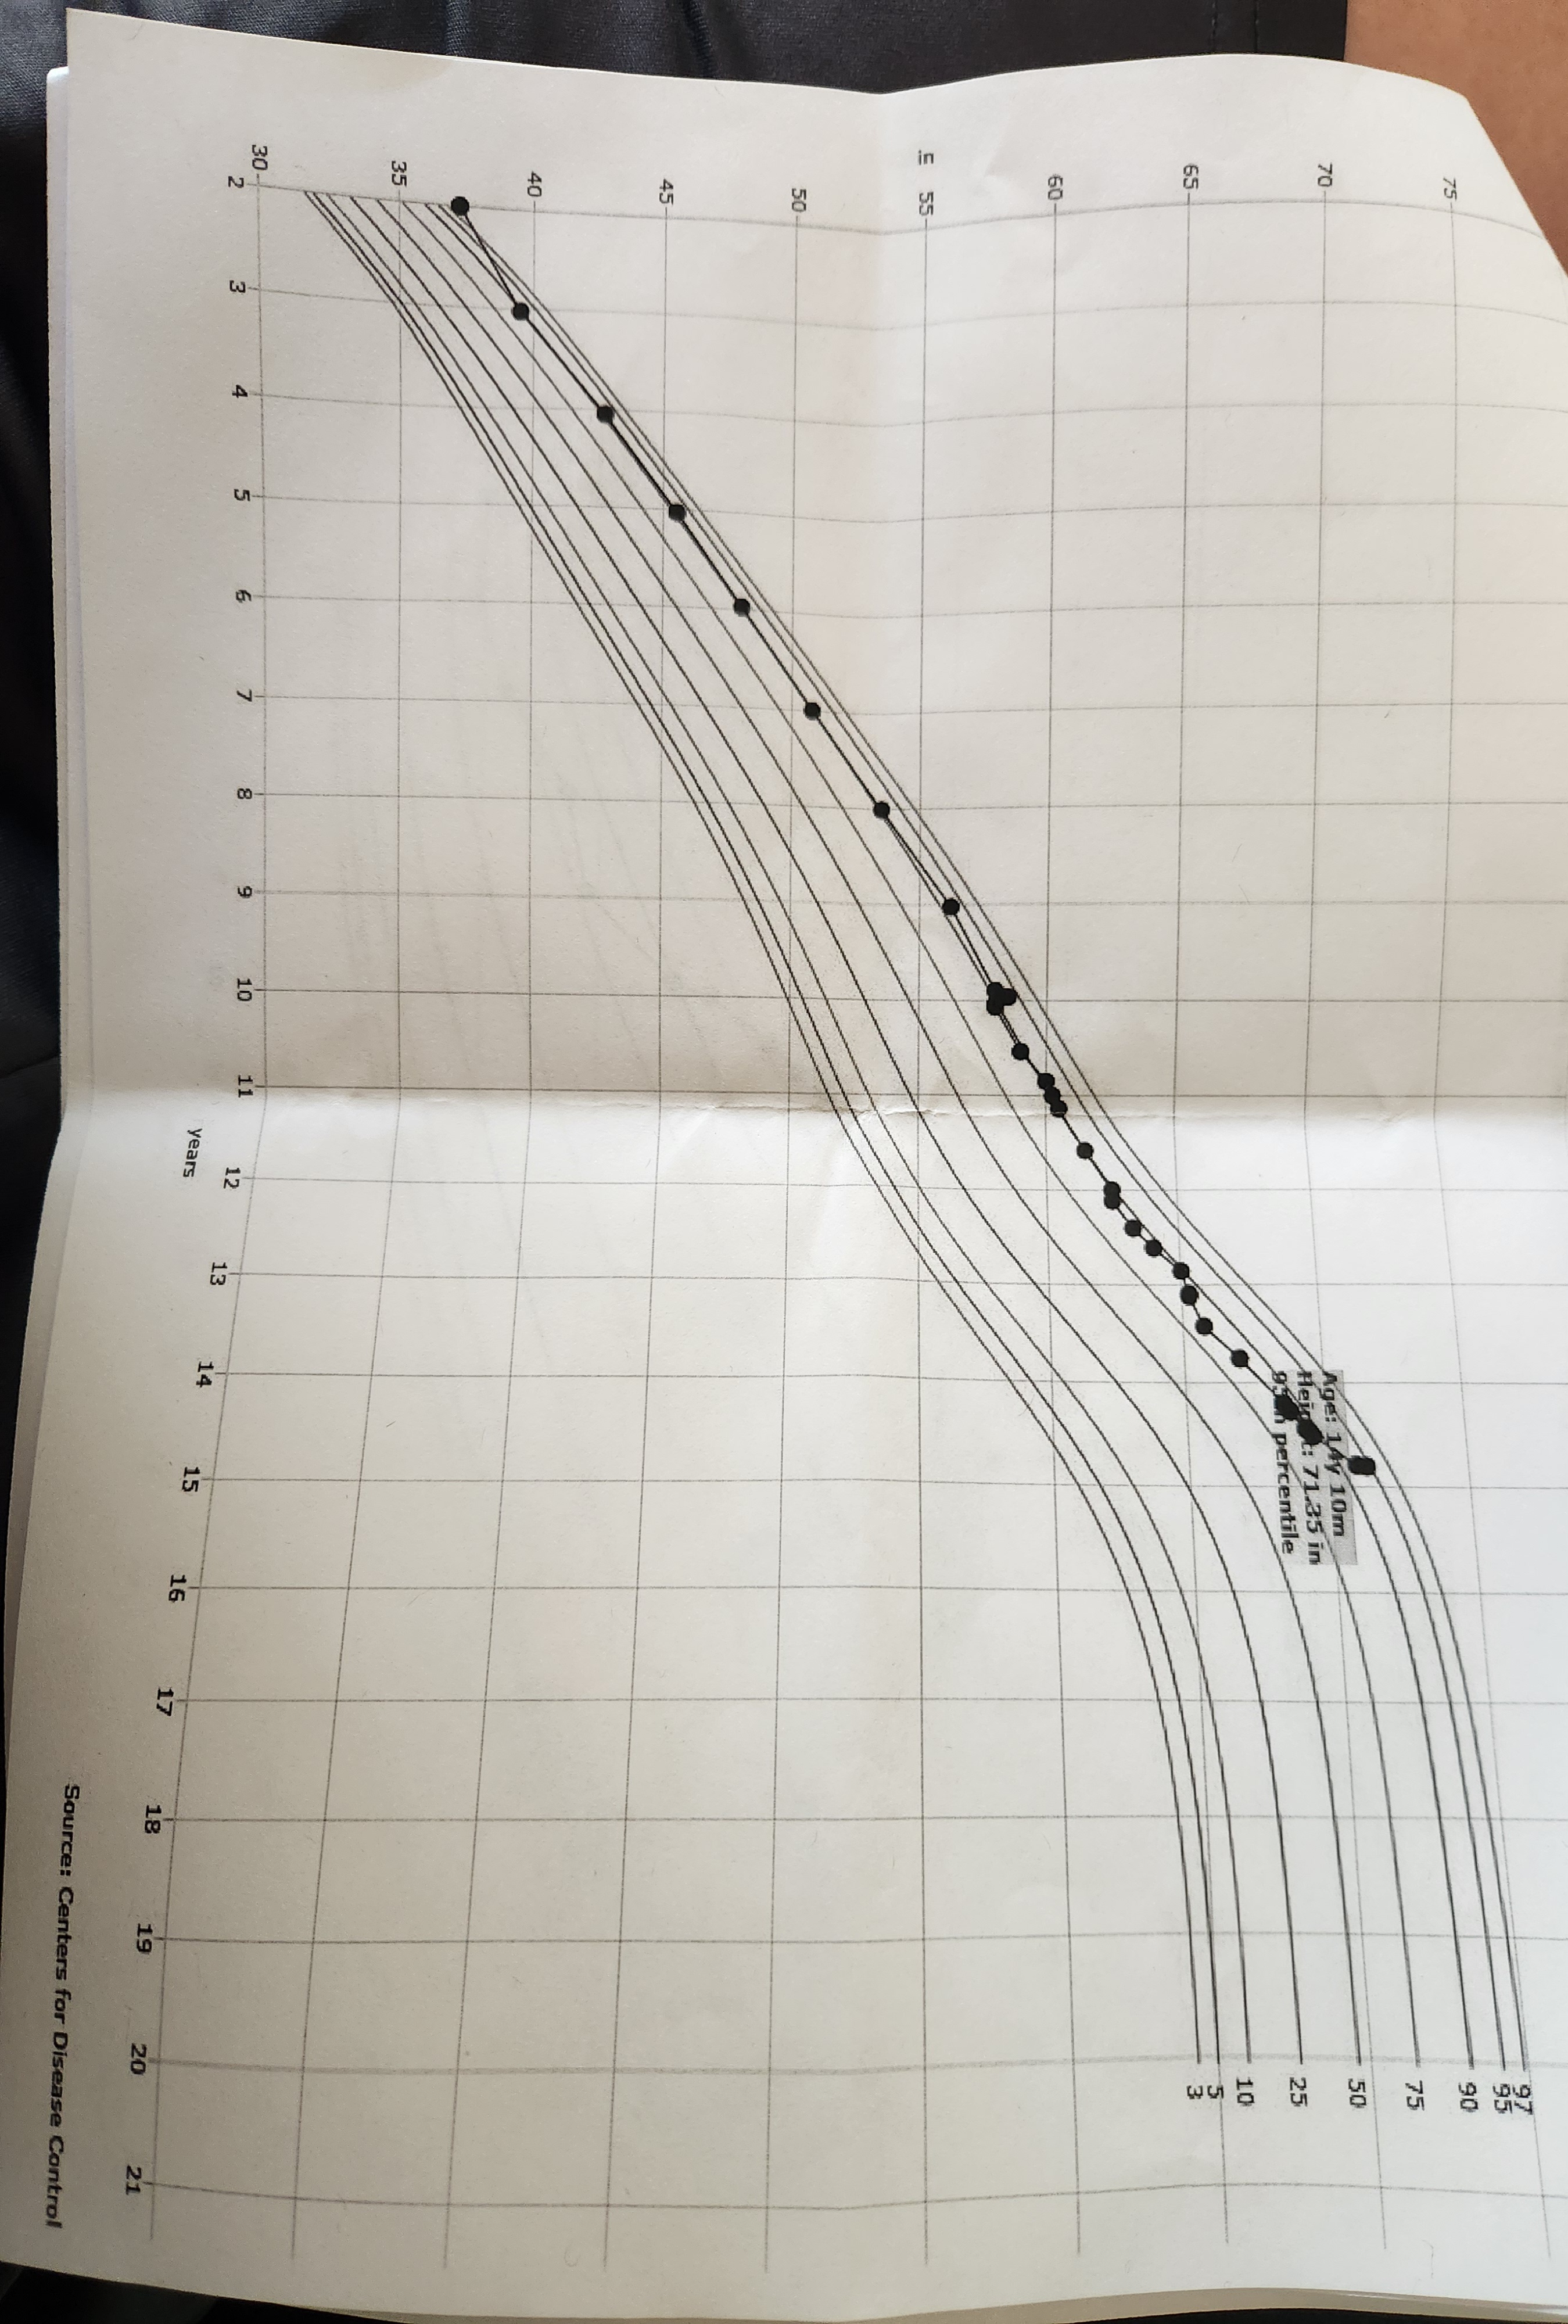

Age now 15 4 months

Height 6'0

xrays and the examination done on October 17

Height 6'0

xrays and the examination done on October 17